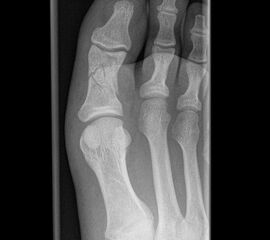

Vorfuß dorsoplantar (dp)

Positionierung:

• Patient liegt auf dem Rücken, der Fuß wird auf die Röntgenkassette aufgestellt, das Knie gebeugt.

• Der Zentralstrahl wird auf das Tarsometatarsalgelenk II zentriert.

• Die Röntgenröhre ist 15° vertikal gekippt.

• Anmerkung: Auch wenn der Fuß nicht belastet wird, sollte er auf die Röntgenkassette aufgestellt werden. Aufnahmen des hängenden Fußes sind nur eingeschränkt beurteilbar.

Kennzeichen des Röntgenbildes:

• Dorsoplantare Abbildung des Vorfußes.

• Tarometatarsale Gelenkreihe einsehbar.

• Winkelmaße können auf der unbelasteten Aufnahme des Vorfußes nicht beurteilt werden.

Besondere Bemerkungen zum Beispielbild:

• Verlaufskontrolle nach korrigierendem Vorfußeingriff bei Riesenwuchs des 2. Strahls mit verdicktem Os metatarsale II.

• Z.n. Amputation des Zehenendglieds D2.

• Z.n. Weil Osteotomie des Os metatarsale II.

• Hallux valgus interphalangeus.

Zur Vollansicht und zum Lesen der Bildbeschreibung bitte die Bilder anklicken.

Vorfuß schräg

• Der Patient sitzt auf dem Untersuchungstisch.

• Der Fuß steht auf der Kassette, der laterale Fußrand wird um 45° angehoben (optional Verwendung eines Keilkissens).

• Der Zentralstrahl wird auf das Tarsometatarsalgelenk III zentriert.

• Die Röhre ist 0° vertikal ausgerichtet.

• Überlagerungsfreie Darstellung der Zehen und Mittelfussknochen, sowie eine gute Beurteilbarkeit der Tarsometatarsalgelenke.

• Der Weichteilmantel ist erkennbar.

• Z.n. Amputation des Zehenendglieds D2